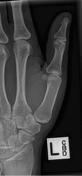

| Oblique Digit | finger not parallel to IR *should be more concave to one side* |

| Oblique Digit | finger not obliqued to 45 degrees - can't see the concavity of one side of the digit joint spaces closed |

| Lateral Digit | finger bent back - not truly lateral |

| Lateral Digit | artifact |

| What's the evaluation criteria for the PA Finger X-Ray? | ANATOMY: distal phalynx -> distal 1/2 of metacarpal demonstrated CRITERIA: - equal concavity on both sides of phalanges - IP and MCP open - no overlapping of adjacent fingers POSITIONING: CR perpendicular @ PIP joint |

| What's the evaluation criteria for the Lateral finger x-ray? | ANATOMY: entire digit demonstrated CRITERIA: open joint spaces concave to one side, while the dorsal side is straight no overlapping of adjacent fingers/soft tissues POSITIONING: CR perpendicular @ PIP joint |

| Oblique finger x-ray image criteria? | ANATOMY: entire digit demonstrated CRITERIA: more concavity to one side open joint spaces no superimposition of adjacent fingers POSITIONING: CR perpendicular @ PIP joint |